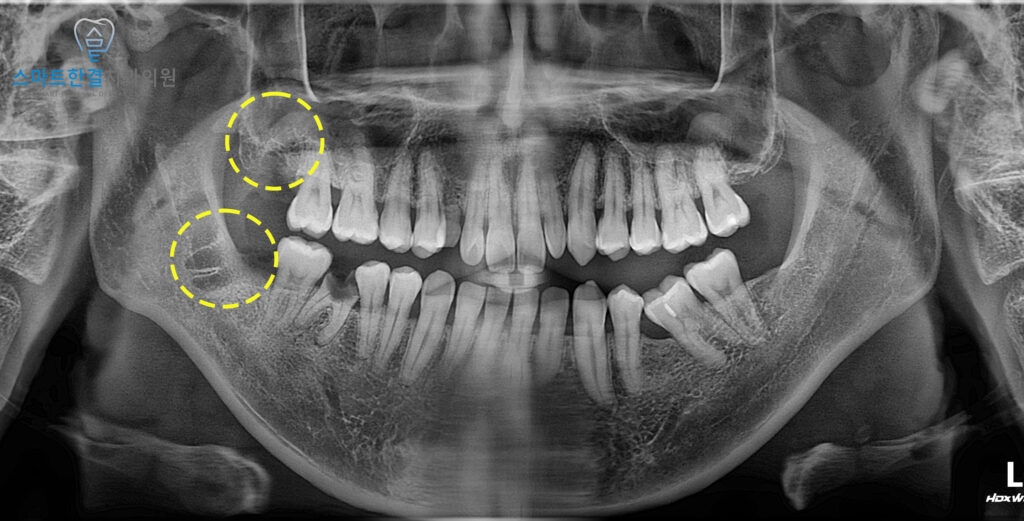

오늘은 오른쪽 위, 아래 사랑니 발치를

진행한 환자분을 소개해 드릴게요.

위쪽 사랑니는 올바르게 자라나있어

불편감이 없었지만

아래 사랑니는 앞 치아 쪽으로

비스듬히 자라나 있어 관리가 안 되어

잇몸이 붓고 그로 인해 앞 치아에

충치가 생길까 걱정되어 내원해 주셨어요.